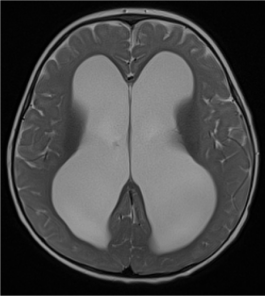

In primary callosal agenesis, white matter tracts that normally cross the midline to form the corpus callosum now reside along the superomedial wall of the lateral ventricles, giving rise to the callosal bundles of Probst. Therefore, the presence of Probst bundles is a strong evidence of primary callosal agenesis (Figure 14 a-c).

Figure 14. Complete primary agenesis of the corpus callosum. Axial T2-weighted image shows colpocephaly (*) and the presence of Probst bundles (white arrows) along the medial margins of the widely spaced lateral ventricles.